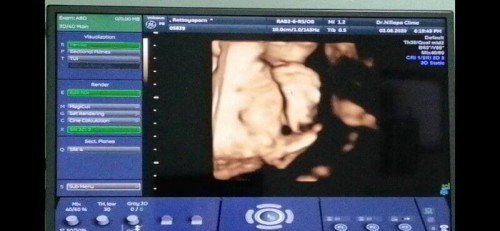

หนูอยู่ในท้องแม่มา 27 วีคแล้วค่ะ วันนี้คุณหมอจะซาวด์ 4มิติให้คุณแม่ดูหน้าหนูว่าจะเหมือนใคร แต่หนูเขินเลยให้แม่ดูฝ่าเท้าน้อยๆของหนูแทน อย่าโกรธหนูนะแม่ ก็หนูเขินนี่คะ 😂 ปล.รูป 2 นี่ไปเจอจากในเฟส สาวน้อยของแม่อยู่ท่านี้เลยค่ะ

บ้านนี้โชว์แต่น้องน้อย 5555 ขี้เขินเหมือนกัน ซาว4มิติทุกเดือนจน9เดือนแล้วไม่เคยไห้เห็นหน้าปิดหน้าตลอดดด แต่อ้าขาโชว์ทุกรอบ (ขี้อายแบบไหนก็ไม่รู้😅😂)

บ้านนี้ปิดตั้งแต่ 22 สัปดาห์ซาวด์ทีไรเป็นแบบนี้ทุกทีค่ะจนตอนนี้ 29 สัปดาห์เสาร์หน้าไปหาหมอหวังว่าจะเปิดให้ดูบ้าง😂#น้องเขิน

บ้านนี้ซาวด์ 4 มิติมา 3 รอบ ปิดหน้าไม่ให้ดูทุกรอบ อิแม่ล่ะเพลีย

บ้านนี้ 27 วีคหมอบอก "น้องนอนกระดิกเท้าสบายใจเลยนะแม่" 😂

บ้านนี้29+5วีค หมอจะให้ดูหน้าลูกเหมือนกันค่ะ แต่ลูกปิดหน้าตลอด 5555

บ้านนี้หมอลองซาวด์ตั้งแต่ 17 วีค น้องปิดตลอดเลยค่ะ

บ้านนี้หมอเขย่าๆอยู่ 2 3 รอบ สุดท้ายหมอบอก "นอนกระดิกเท้าสบายใจไม่สนเลยแม่ อดดูหน้าเลย" 😂

บ้านนี้ก๋เอามือปิดหน้า ปิดปาก ไปซาว 2 ครั้ง ไม่คุ้มเงินเลยคะ